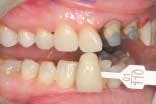

The next image of the arches slightly open allows the patient to see the lower anterior teeth, which are often covered by the maxillary teeth. This also allows us to evaluate the arch form and the curve of Spee and Wilson. A neuromuscular arch incoordination will begin to show as one side of the mandibular arch may drop more than the other side. This shot can be captured with a shade tab in the same plane with the maxillary incisors to demonstrate the shade to patient.